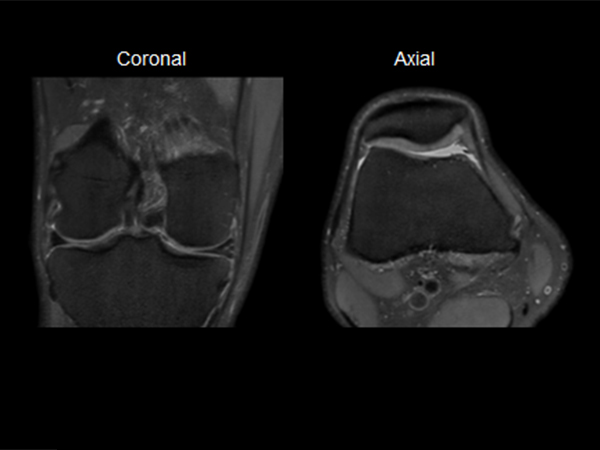

Knee imaging